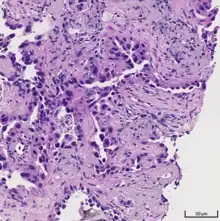

Histopathology of lepidic predominant adenocarcinoma.

Acinar pattern.[16]

Solid pattern.[17]

• lepidic predominant [18]

• acinar predominant [19]

• papillary predominant [20]

• micropapillary predominant [21]

• solid predominant with mucin production [22]

Cell patterns identifying subtypes are associated with prognosis, ranging from favorable (lepidic) to intermediate (acinar and papillary) to poor (micropapillary and solid).[2]

As discussed previously, the category of adenocarcinoma includes are range of subtypes, and any one tumor tends to be heterogeneous in composition. Several major subtypes are currently recognized by the World Health Organization (WHO)[1] and the International Association for the Study of Lung Cancer (IASLC) / American Thoracic Society (ATS) / European Respiratory Society (ERS):[30][31][32] lepidic predominant adenocarcinoma, acinar predominant adenocarcinoma, papillary predominant adenocarcinoma, micropapillary predominant adenocarcinoma, solid predominant adenocarcinoma, and solid predominant with mucin production. In as many as 80% of these tumors, components of more than one subtype will be recognized. Surgically resected tumors should be classified by comprehensive histological subtyping, describing patterns of involvement in increments of 5%. The predominant histologic subtype is then used to classify the tumor overall.[2] The predominant subtype is prognostic for survival after complete resection.[33]